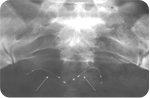

Three months after the Essure® procedure, the gynecologist performs an Essure Confirmation Test to confirm the correct position of the implants and that the tubes are completely blocked thus indicating permanent contraception. The Confirmation Test is carried out via an x-ray of the abdomen or an ultrasound scan of the uterus. The implants can be viewed and assessed as to their position and whether or not the tubes are completely blocked. When the test confirms that the implants are well positioned and the tubes are blocked then test results show that the woman has zero chance of falling pregnant.

- Three months after the procedure, the gynecologist performs a confirmation test. The abdomen is x-rayed and an ultrasound scan is normally retaken. When the confirmation test is positive then there is no need to continue taking other forms of birth control as this sterilization procedure is deemed successful. Failure rates are 0.05% after one year and 0.02% after 4 years. Up to now at our centre, no patient has fallen pregnant after a successful Essure® procedure.